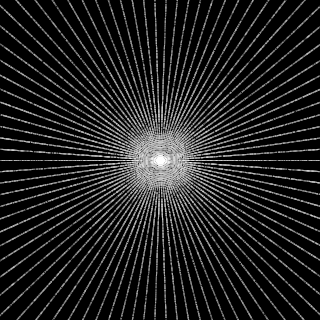

This article presents a novel undersampled magnetic resonance imaging (MRI) technique that leverages the concept of Neural Radiance Field (NeRF). With radial undersampling, the corresponding imaging problem can be reformulated into an image modeling task from sparse-view rendered data; therefore, a high dimensional MR image is obtainable from undersampled $k$-space data by taking advantage of implicit neural representation. A multi-layer perceptron, which is designed to output an image intensity from a spatial coordinate, learns the MR physics-driven rendering relation between given measurement data and desired image. Effective undersampling strategies for high-quality neural representation are investigated. The proposed method serves two benefits: (i) The learning is based fully on single undersampled $k$-space data, not a bunch of measured data and target image sets. It can be used potentially for diagnostic MR imaging, such as fetal MRI, where data acquisition is relatively rare or limited against diversity of clinical images while undersampled reconstruction is highly demanded. (ii) A reconstructed MR image is a scan-specific representation highly adaptive to the given $k$-space measurement. Numerous experiments validate the feasibility and capability of the proposed approach.